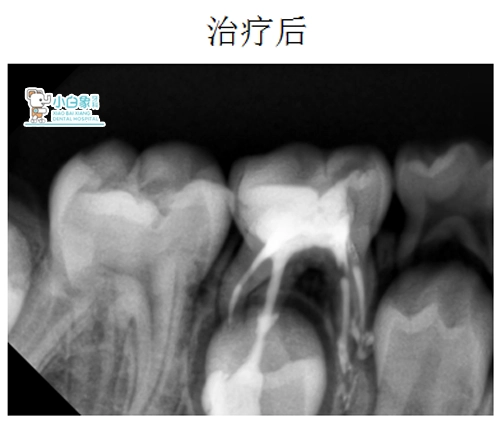

治疗:85去腐露髓,封慢失一周。复诊开髓揭顶,拔髓,清理根管,冲洗,隔湿干燥,根管内置Vt,磷酸锌垫底,Z250充填。

QQ截图20181220151738

QQ截图20181220151744